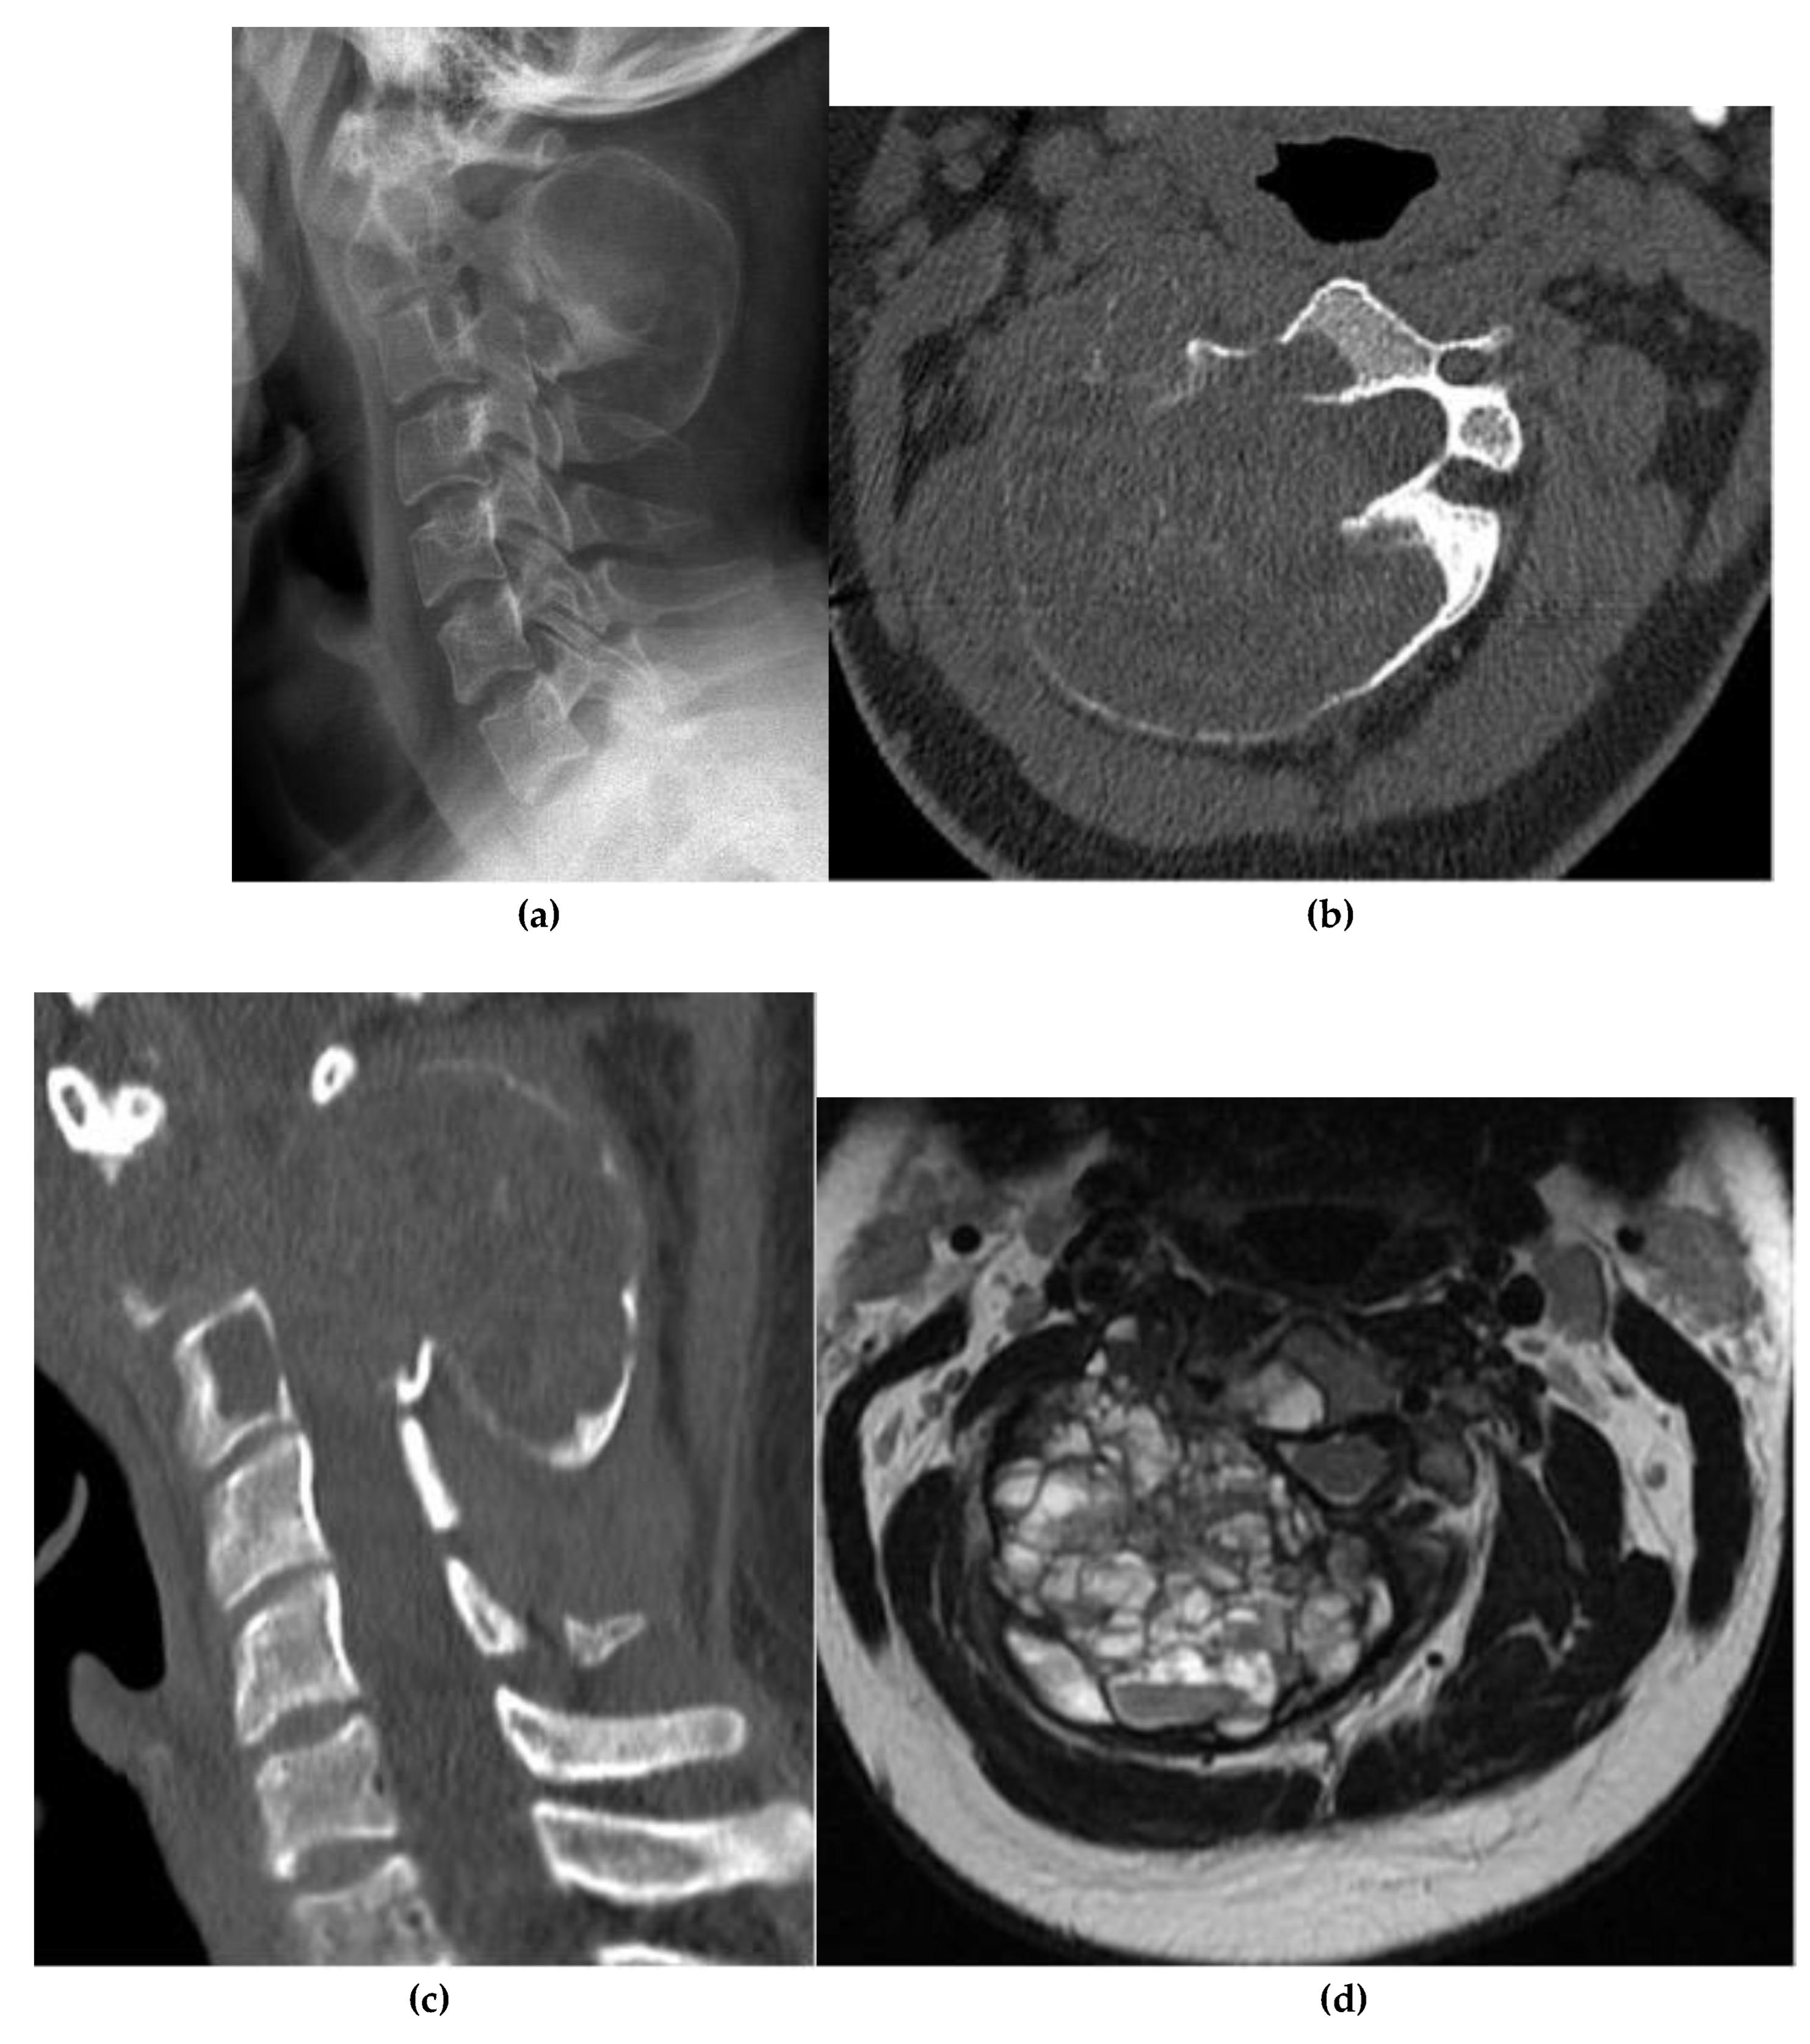

Chordoma